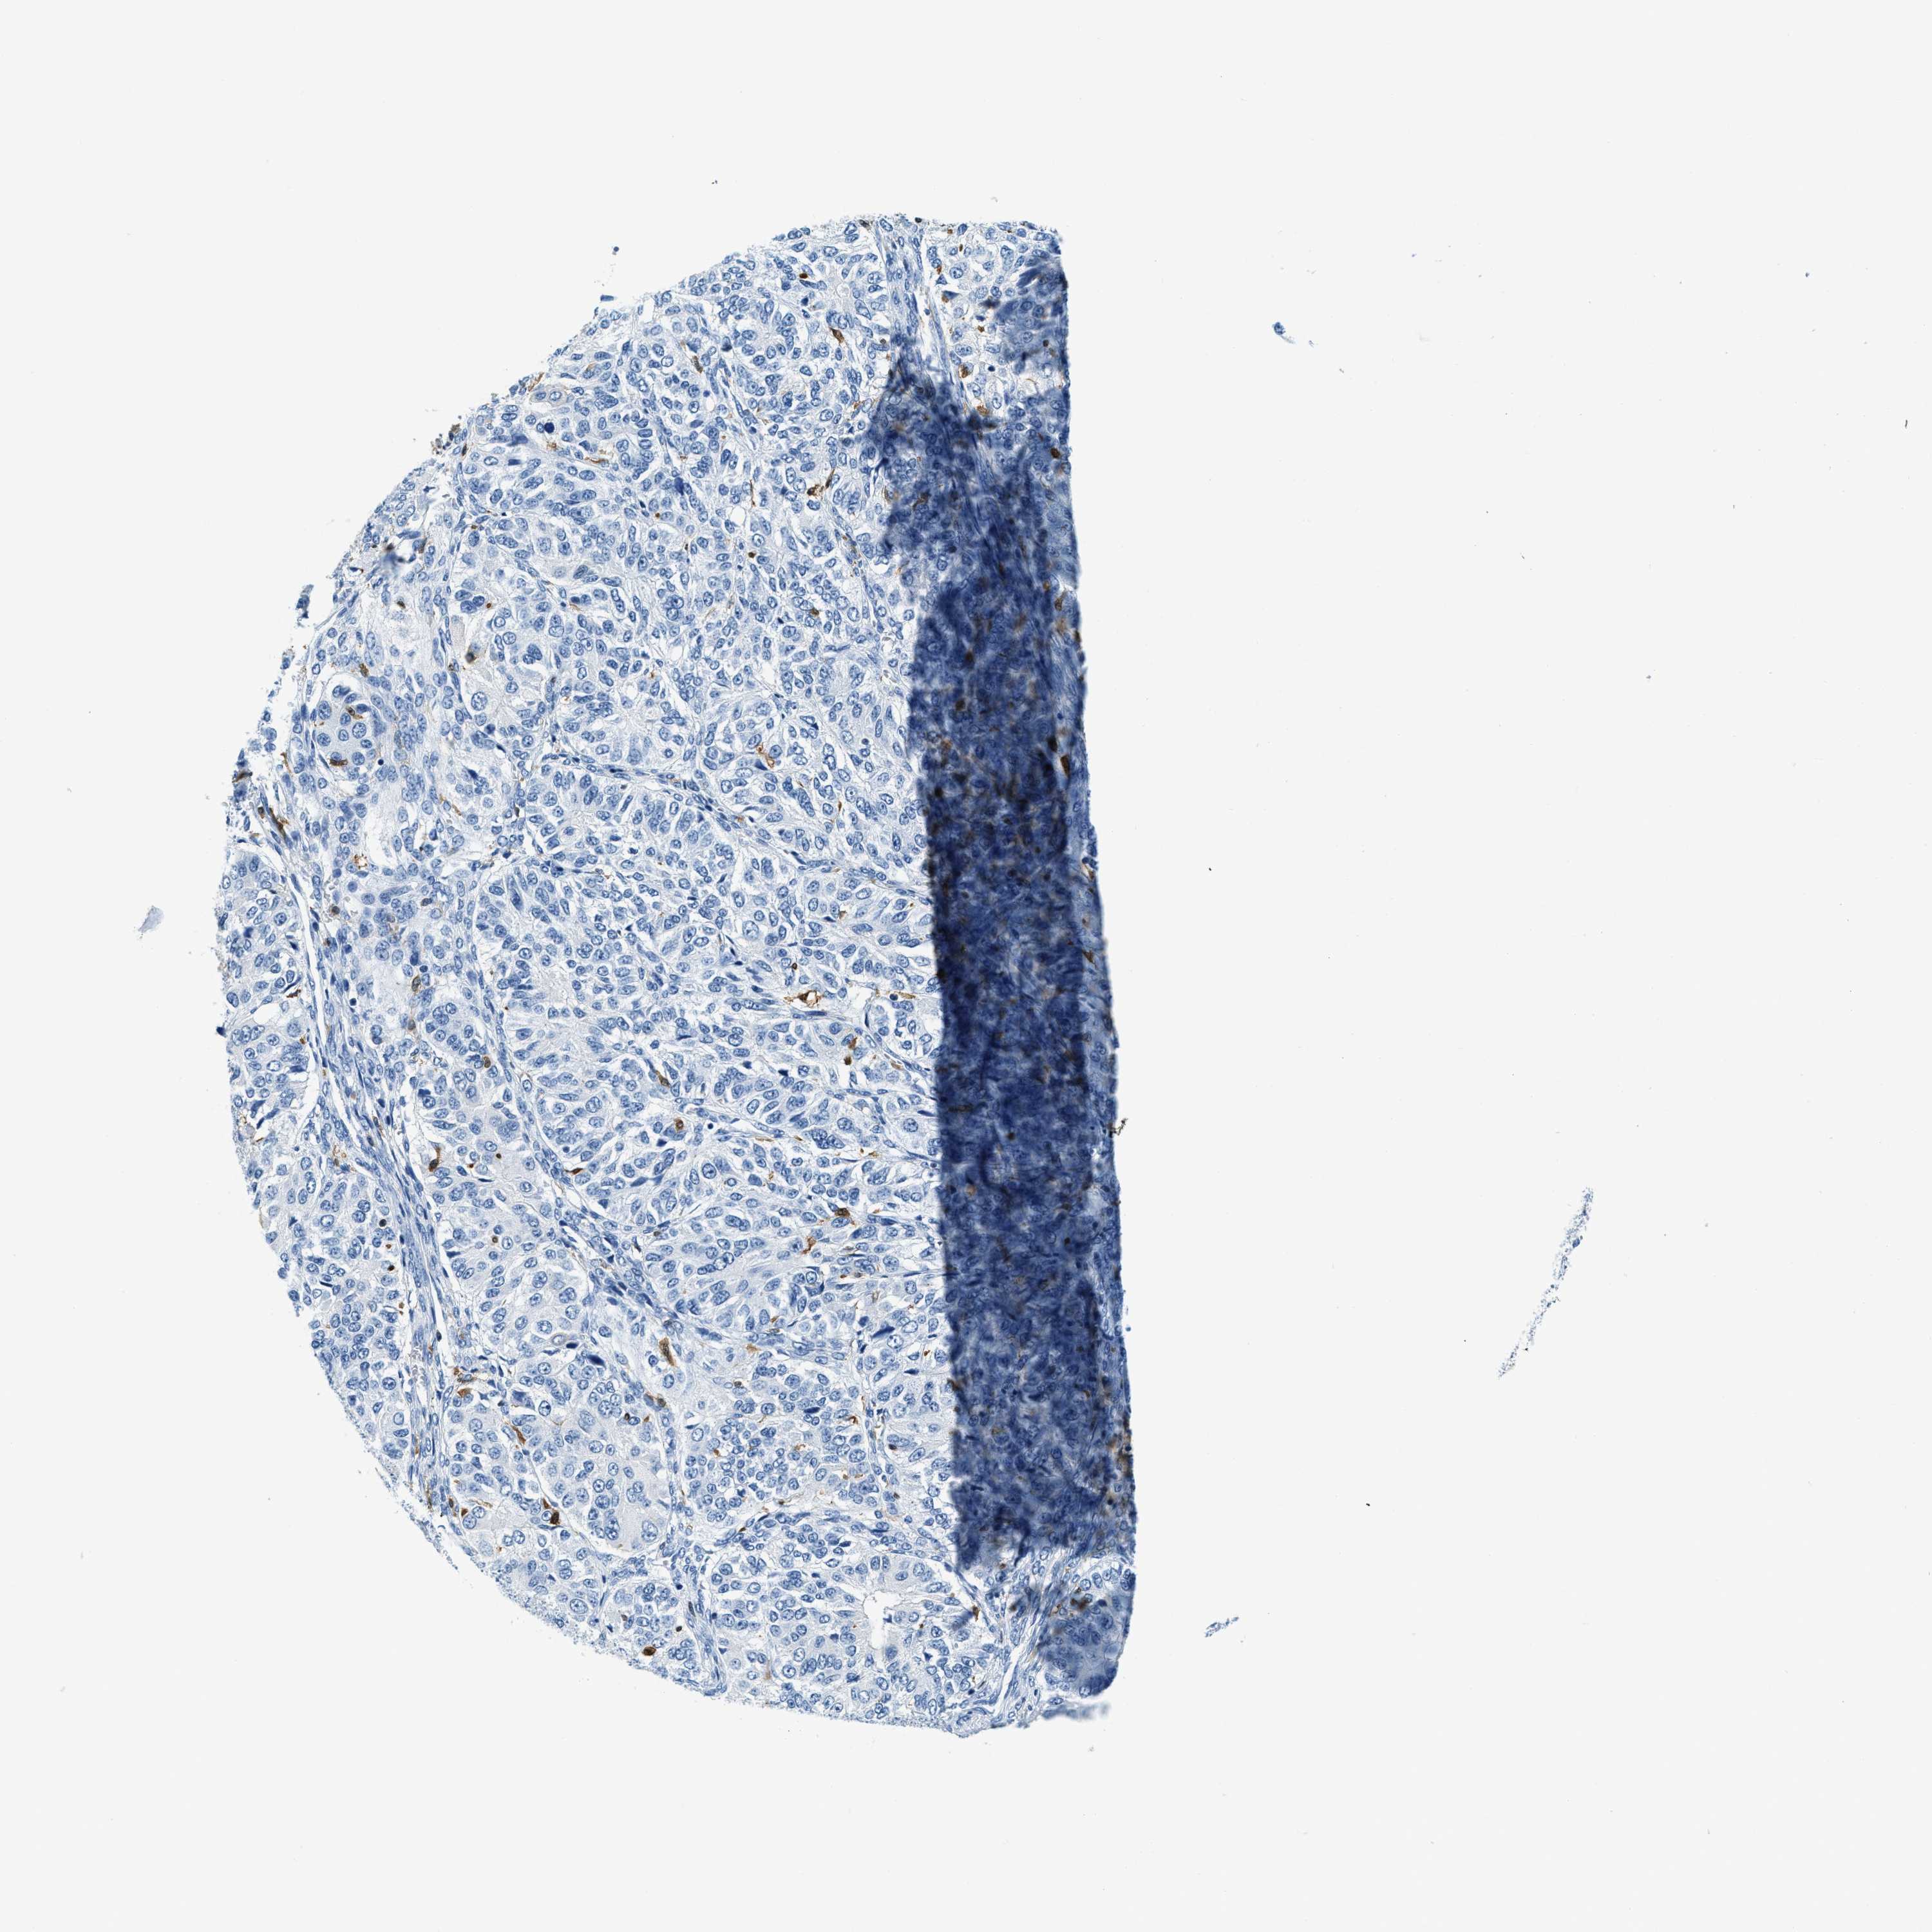

OVARIAN CANCER - Protein expressioni

A mouse-over function shows sample information and annotation data. Click on an image to view it in a full screen mode. Samples can be filtered based on level of antibody staining by selecting one or several of the following categories: high, medium, low and not detected. The assay and annotation is described here.

Note that samples used for immunohistochemistry by the Human Protein Atlas do not correspond to samples in the TCGA dataset.

Antibody stainingi

Antibody staining in the annotated cell types in the current human tissue is reported as not detected, low, medium, or high, based on conventional immunohistochemistry profiling in selected tissues. This score is based on the combination of the staining intensity and fraction of stained cells.

Each image is clickable and will lead to virtual microscopy that enables deeper exploration of all samples and also displays staining intensity scores, fraction scores and subcellular localization as well as patient and tissue information for each sample.

Antibody HPA018843

Antibody HPA019080

Antibody HPA019092

Staining

High

Medium

Low

Not detected

Intensity

Strong

Moderate

Weak

Negative

Quantity

>75%

75%-25%

<25%

None

Location

Nuclear

Cytoplasmic/membranous

Cytoplasmic/membranous,nuclear

Cystadenocarcinoma, serous, NOS

Carcinoma, endometroid

Cystadenocarcinoma, mucinous, NOS

Carcinoma, NOS